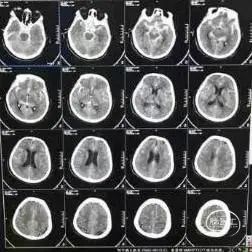

入院查头颅CT显示:蛛网膜下腔出血,脑室内积血,桥脑软化灶,左颧骨骨瘤。

术前影像

术前CT显示:蛛网膜下腔出血。